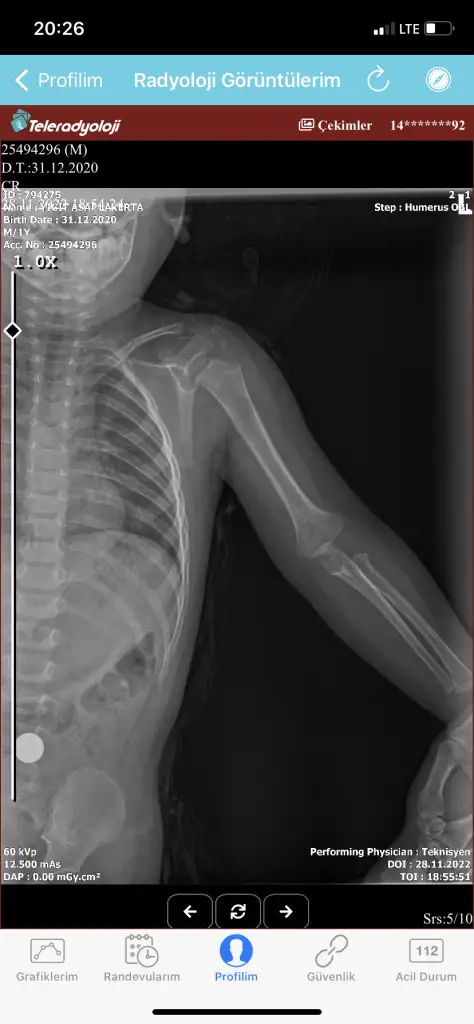

Lütfen yardım! 2 yaşında oğlum köprücük kemiği kırıldı.

Alçıya almadılar bandajla sardılar ilk defa başıma geliyor. Ağrı kesici veya başka bişey ne kullanmam lazım. Sabit de durmuyo çocuk hareketli sürekli. Başına gelip çabuk iyileşen oldu mu ?

Geçmiş olsun, 1.5 yaş civarında abimin başına gelmiş. Dediğiniz gibi o zamanlarda alçı falan yapılmıyormuş. Ve gene dediğiniz gibi, abim de çok hareketliymiş. :)) Hiçbir problem olmadan, kendi kendine kaynamış ve daha sonra da sorun çıkarmadı. Ne kadar zamanda iyileşmiş, söylendiyse de hatırlamıyorum maalesef. Umarım en kısa sürede iyileşir oğlunuz.

Kuzenin başına 22 yaşında geldi bandaj sarıldı sanırım 1,5 ayda toplar